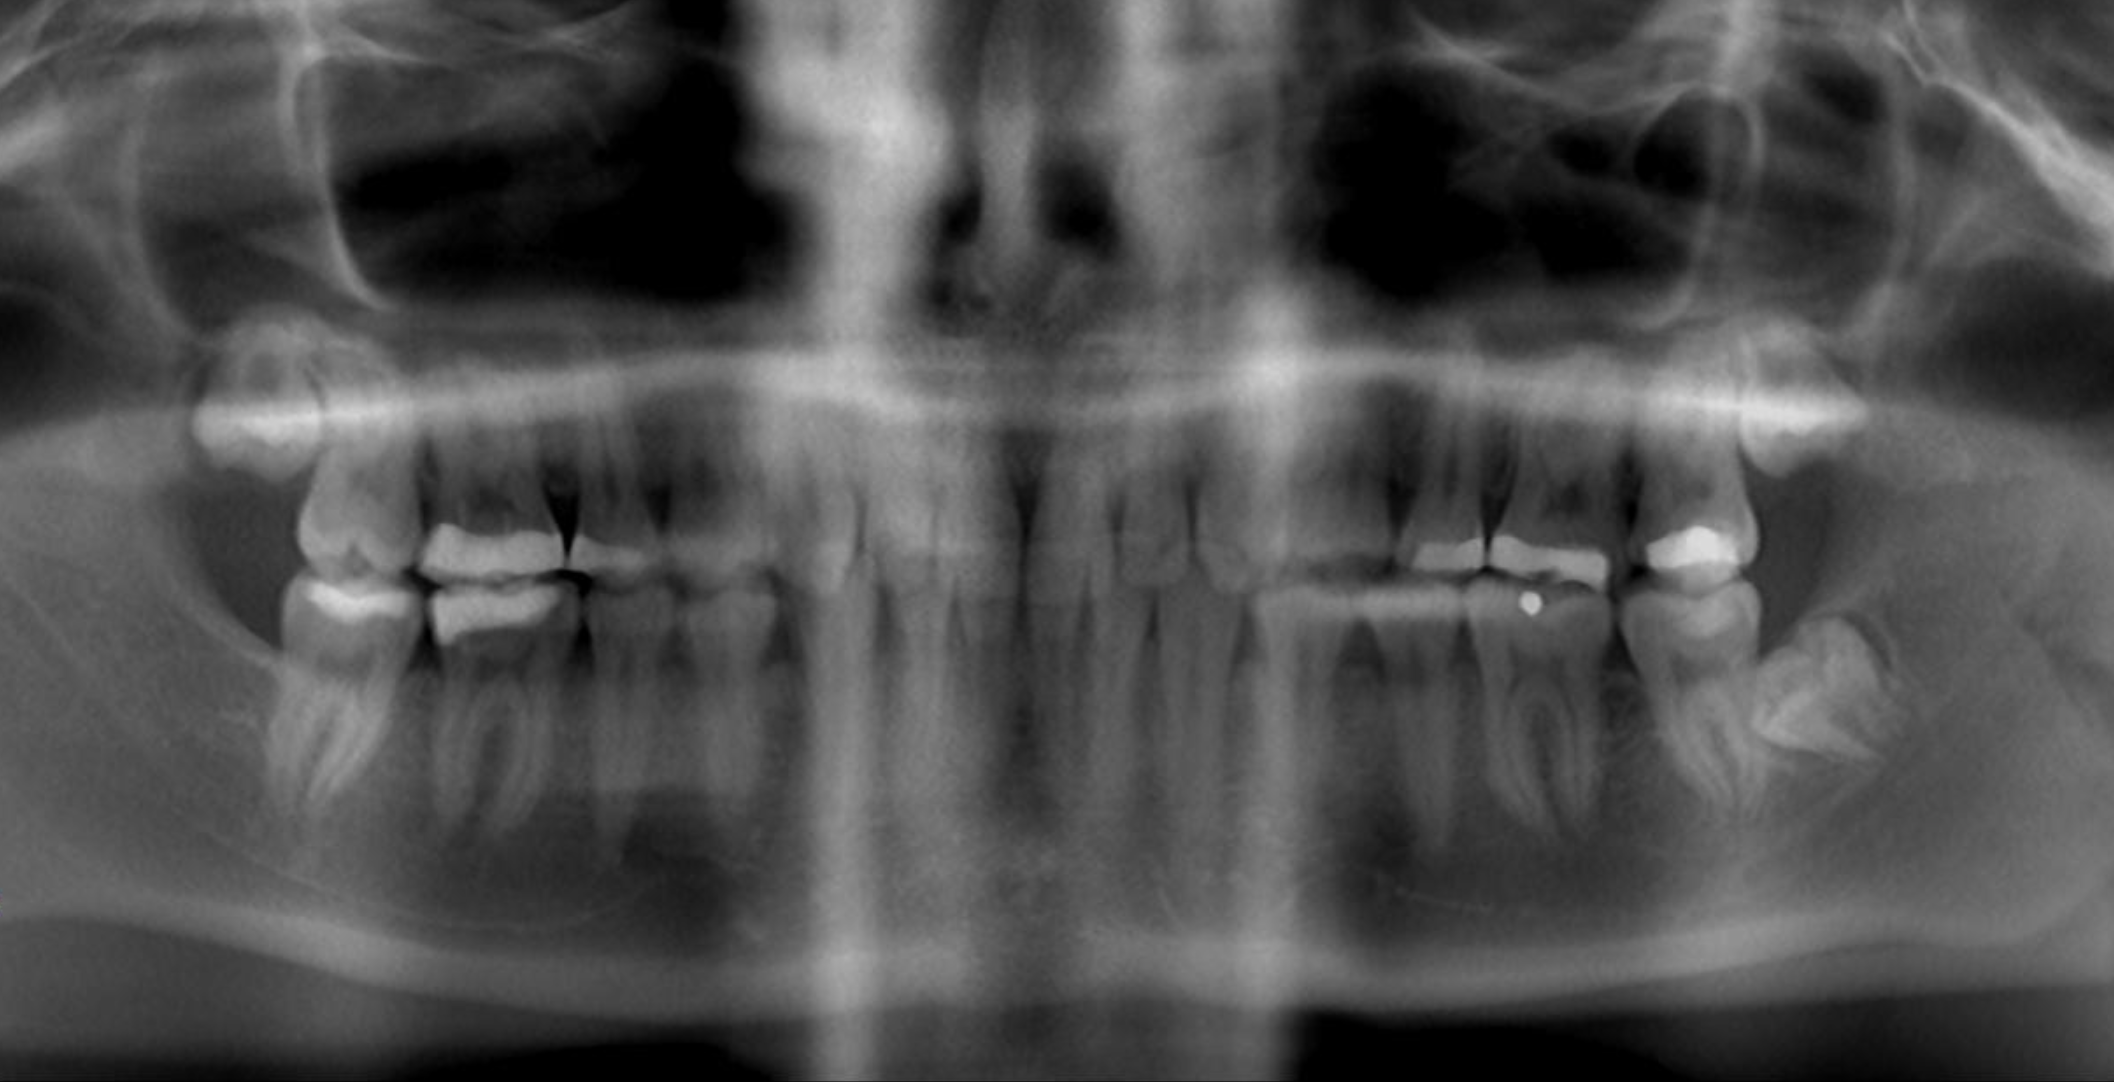

A young man presented with a fractured maxillary left-central incisor on a Monday morning after a Saturday evening discussion that did not end well (Figure 1). Visual oral examination and palpation of the structures revealed mobility of 3+, pain on palpation and percussion, a thick soft-tissue profile, and a low lip line. Gingival zeniths were irregular, there was a class II division 2 deep bite, and the periodontium was healthy overall (Figure 2 through Figure 4). Radiographs requested at the time of the initial visit were periapicals, panoramic, and CBCT images (Figure 5 and Figure 6). After all images and information were reviewed and the extent of his injury was discussed, the patient was presented with the following options: removable prosthetics, fixed partial denture, extract and do nothing, or extract and place a dental implant with bone augmentation.

Fig 5. Preoperative panoramic.

Figure 5